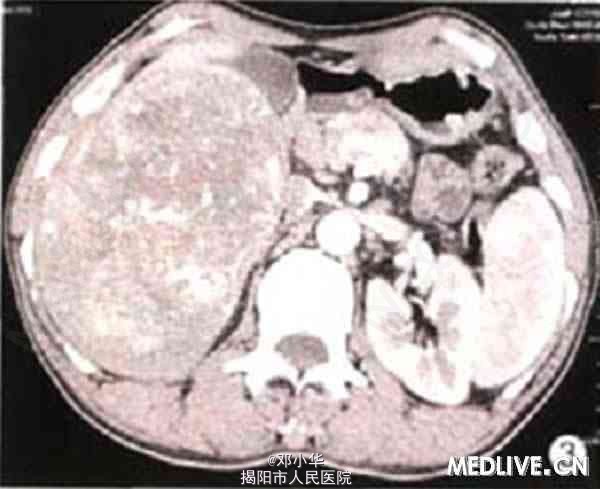

体格检查:体温正常,无消瘦、乏力,皮肤巩膜无黄染,上腹未及肿块,肝肋下3指,脾未扪及。 实验室检查:肿瘤指标正常;乙肝病毒表面抗原(HBsAg)、乙肝病毒e抗体(HBeAb)、乙肝病毒核心抗体(HBcAb)均阳性;。碱性磷酸酶(ALP)521.5 U/L。谷氨酰转肽酶(GGT)180 U/L,丙氨酸氨基转移酶(ALT)85 U/L。 超声检查示右肝内见12.7cm×12.2 cm的实质性肿块(图1)。边界清,无声晕,内部回声强弱不均。低机械指数成像技术下SonoVue超声造影显示动脉期10 s时肿块大部分迅速增强,高于同期肝实质,25 s后大部分消退(图2)。低于同期肝实质,提示恶性病变(肝癌)。 腹部CT示肝增大,右叶一巨大肿块(图3),大小约9.8 cm×13.2 cm。CT提示肝恶性肿瘤,首先考虑肝细胞性肝癌伴淋巴结转移,伴肺部转移,矽肺待排。

临床诊断:原发性肝细胞癌,伴两肺转移,腹部、纵膈淋巴结转移;乙型肝炎;早期肝硬化;右肝动脉变异。 手术所见:肝色泽暗红。肝包膜光整,表面无结节,质地柔软,肝右叶一肿块大小约14 cm×12 cm,有包膜,质地中等,压之不缩小,表面血管轻度扩张,肿块内呈灰白色为主,肝右侧与侧腹膜广泛粘连,肝十二指肠韧带及腹主动脉旁多枚淋巴结肿大。质软。 病理结果:镜下细胞呈梭形,略旱编织状排列,大量淋巴细胞、浆细胞和嗜酸粒细胞等浸润,纤维组织增生,内有大片状炎性坏死灶,肿块与肝之间有纤维包膜分隔。